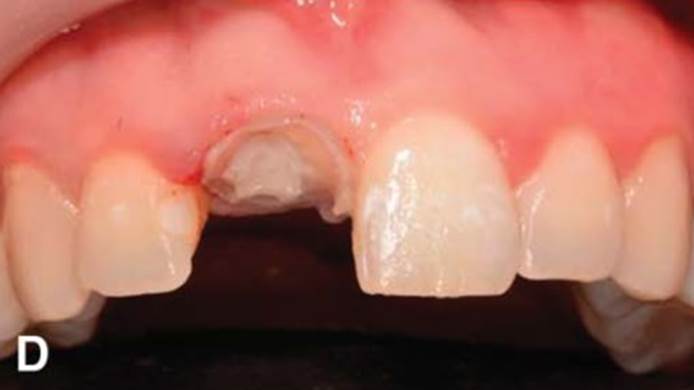

Clinical case: Immediate post-extraction insertion of implant & immediate loading

- Courtesy of Prof. Giuseppe Luongo, Italy -

AnyRidge, immediate loading, single implant, multicenter study, maxillary anterior, Prof. Giuseppe Luongo, single replacement

AnyRidge implant system

Clinical case: Replacement of fractured central incisor (#11) with immediate implant

& Root Membrane Technique

- Courtesy of Dr. Miltiadis Mitsias, Greece -

AnyRidge, Root Membrane Technique, retrospective study, long-term study, immediate implants, bone resorption, bone preservation, Dr. Miltiadis Mitsias,survival, success, maxillary anterior, single replacement

AnyRidge implant system, Root Membrane kit

The Root Membrane Technique: A retrospective clinical study with up to 10 years of follow-up./Implant Dent. 2018 Oct;27(5):564-574